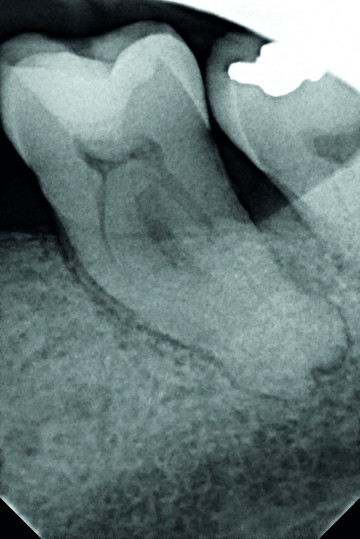

Dr Tara Mc MAHON, Belgium - 1/3 Preoperative x-ray Apical periodontitis, tooth n°37